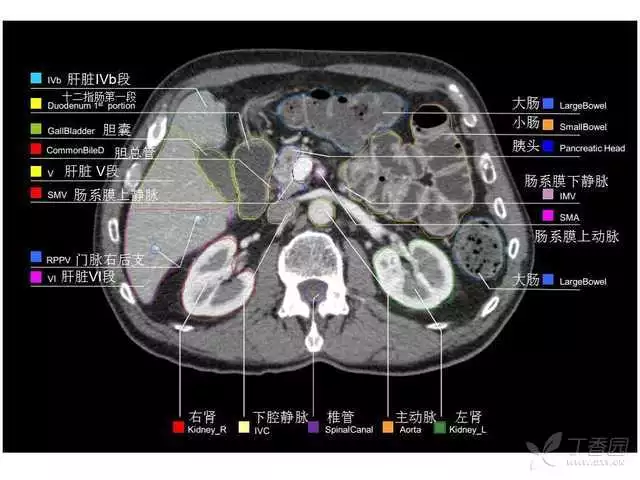

其实你离掌握上腹部 CT 影像只有一套高清实用图谱的距离,下面把我最喜欢的这本图谱分享给大家,为了方便阅读,我加了中文标识。后面附赠几张血管相对位置解剖关系图片,帮助大家理解(文中多图,建议在 wifi 环境下查看)。